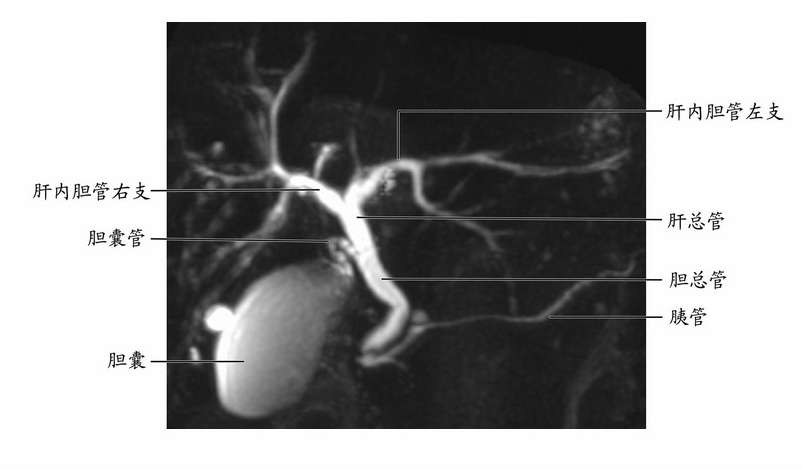

MRCP 使用高度 T2 加权的 MRI 脉冲序列。 这些序列在胆囊、胆管和胰管内的静态或缓慢移动的液体中显示高信号,而周围组织的信号低。 分泌素也被给予患者以增加导管顺应性,使成像更容易。

- MRCP 正常(可见肾囊肿)